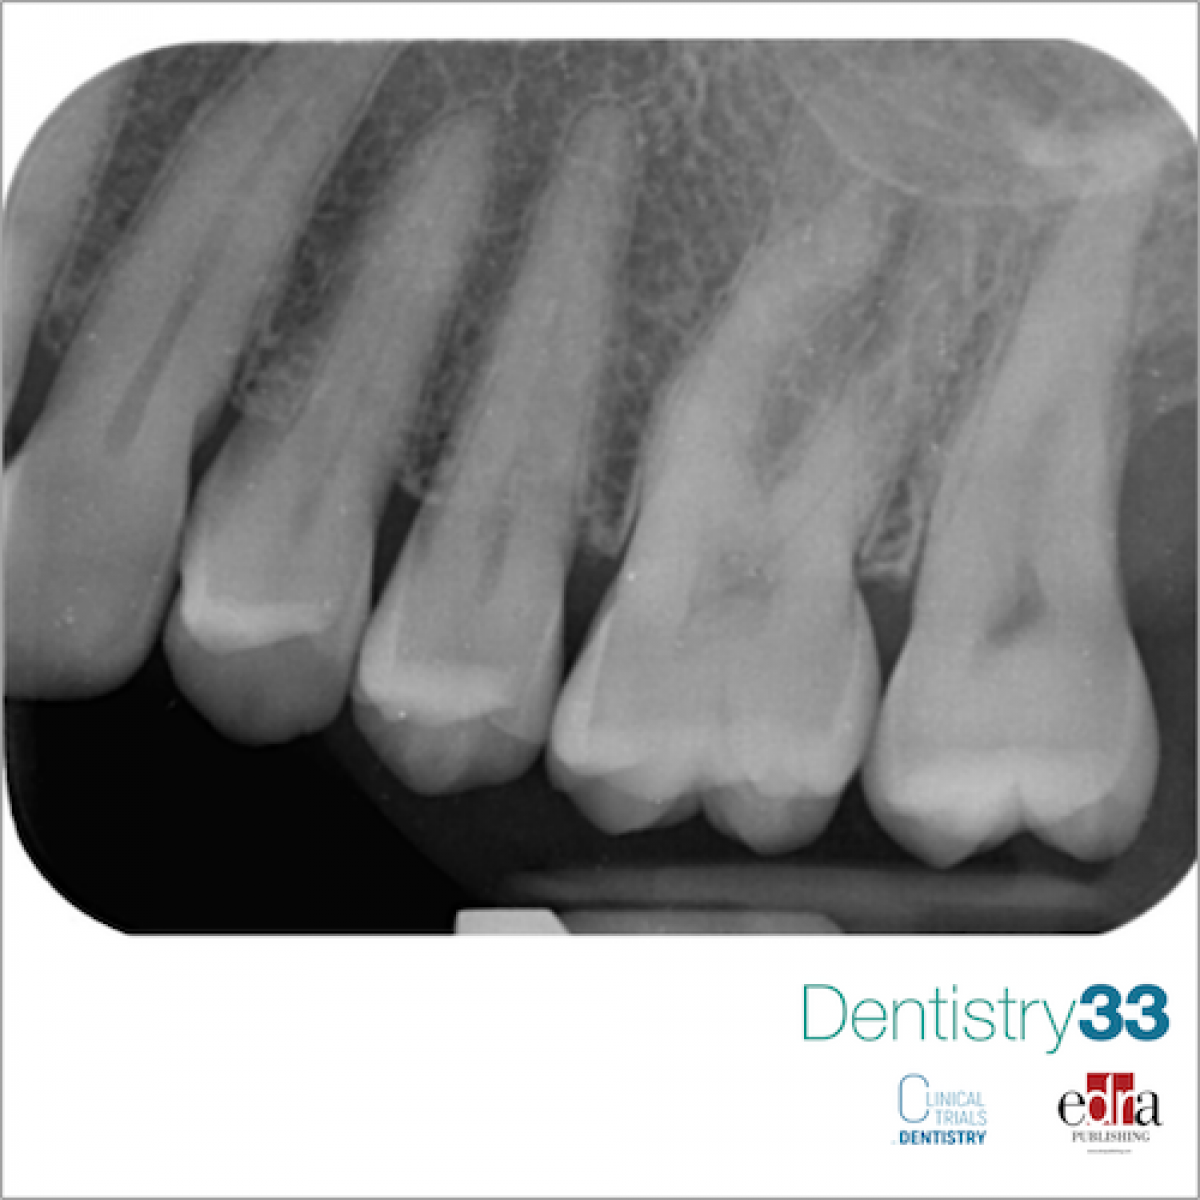

The intraoral periapical examination (Fig. 1) reveals bone resorption at the distal root of element 2.7. The periodontal examination shows probing on the distal side and the vestibular side, with exudate.